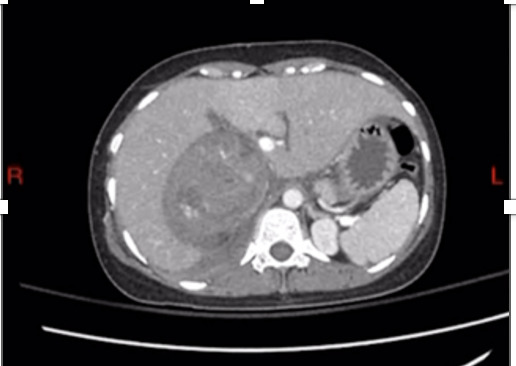

Initial basic investigations were performed and said to be normal. Liver function test (LFT) revealed alteration in enzymes and bilirubin levels, such as - AST -378, ALT – 366, GGT – 403, ALP – 433, Serum Albumin – 3.1 g/dL (3.5 - 5) and Total Bilirubin – 6.5 mg/dL (0.3 – 1.2) with direct fraction of 3.6 mg/dl. Serological tests for hepatitis B virus (HBV) and hepatitis C virus (HCV) were negative. Immunological assays for the various auto-immune diseases (ANA, anti-ssDNA, ASMA, p-ANCA and c-ANCA) were all negative. The urine analysis showed hematuria, blood and urine cultures were sterile. Ultrasound scan demonstrated large (10x6cm) heterogenous right renal mass suggestive of Angiomyolipoma and for further information, a contrast CT was performed. Computed tomography (CT) revealed 11x11x10 cm heterogeneously enhancing lesion arising from upper pole of right kidney suggestive of Renal cell carcinoma without any renal vein or inferior vena cava (IVC) thrombus and no paraaortic lymphadenopathies.